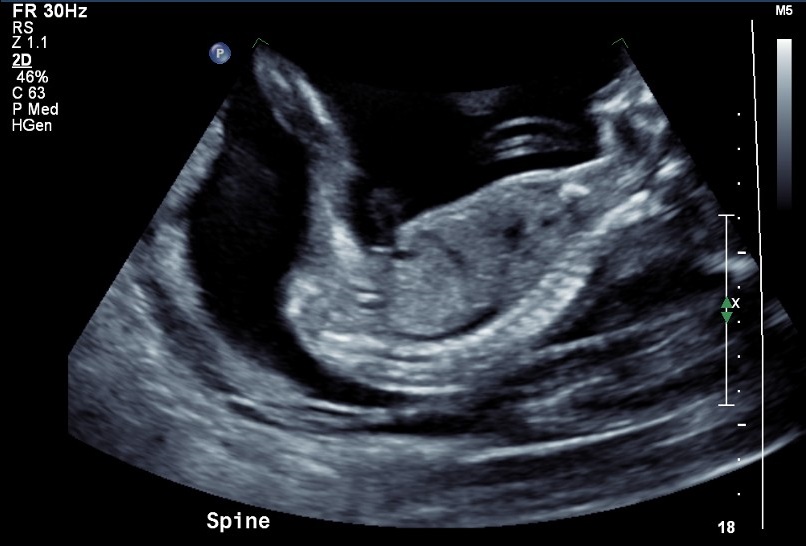

I went for my 20 week scan today and came out a bit disappointed I was not provided any potty shots to take they would only give me these 2 pics. The lady did say she thinks it's a girl but can't confirm and based on her inexperience I'm skeptical to say the least .

I'm looking to go get another scan and hopefully get better pictures, in the mean time please let me know your thoughts on these 2 I know they are mostly face but I thought I would ask anyway :)Attachment 33276Attachment 33277